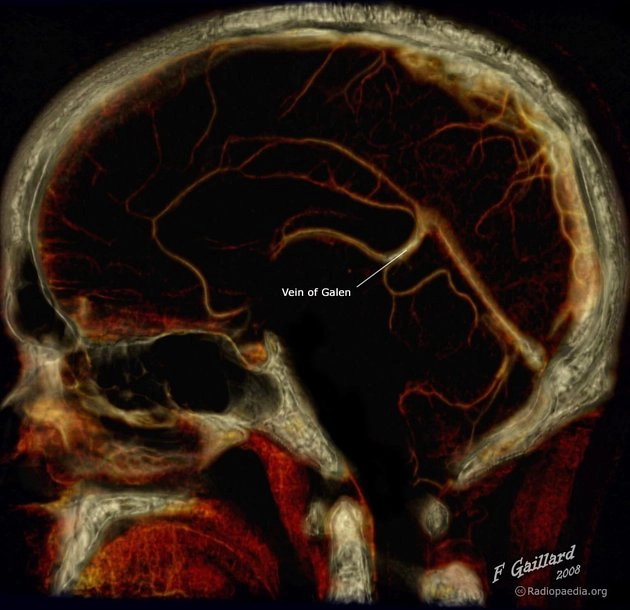

• Phân loại Yasargil cho dị dạng phình tĩnh mạch Galen (Yasargil classification of vein of Galen aneurysmal malformations)

• Dị dạng phình tĩnh mạch Galen (Vein of Galen aneurysmal malformations - VGAMs)